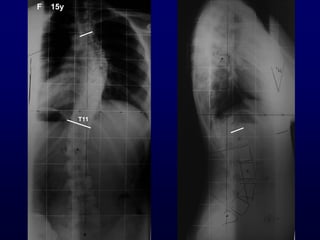

F 15y

T11